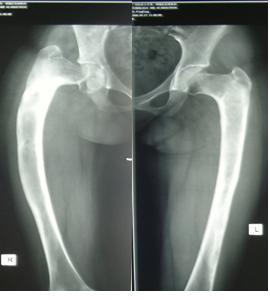

图6 女性,21岁,双侧DF 图7 术后5年力线正常,截骨愈合好